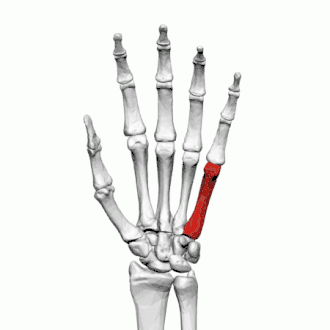

Cinquième métacarpien

Description

Le cinquième métacarpien est plus court que le quatrième métacarpien.

Base

Sa face supérieure présente une surface articulaire concavo-convexe qui s'articule avec l'hamatum.

Sa face radiale présente une facette articulaire qui s'articule avec le quatrième métacarpien.

Sa face ulnaire présente un tubercule pour l'insertion du muscle extenseur ulnaire du carpe.

Corps

La surface dorsale du corps est divisée par une crête oblique, qui s'étend du côté ulnaire de la base jusqu'au côté radial de la tête. Sur la partie latérale s'insère le quatrième muscle interosseux dorsal de la main, la partie médiale est lisse, triangulaire et couverte par les tendons extenseurs du petit doigt.

La surface palmaire est divisée de la même manière : la partie latérale est l'origine du troisième muscle interosseux palmaire, la partie médiale donne insertion au muscle opposant de petit doigt.